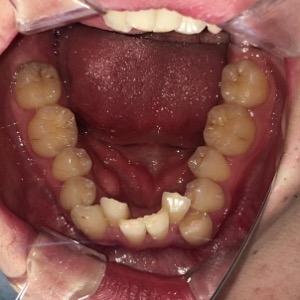

症例

before

患者さんの年齢 30代 男性 症状 ガタガタを治したい 治療内容 ワイヤー矯正治療 費用 88万(税抜) 治療期間・回数 治療期間2年半、通院回数20回 メリット 口元が綺麗 デメリット・リスク 期間がかかることがある 患者さまの声 見た目が良くなった - 矯正治療